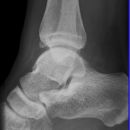

Sprunggelenk

Weber A

Es wurden keine Bilder gefunden.

Weber B

Weber C + dorsales Volkmann

Trimalleoläre

Vorderes Volkmann + lat. Talusschulter